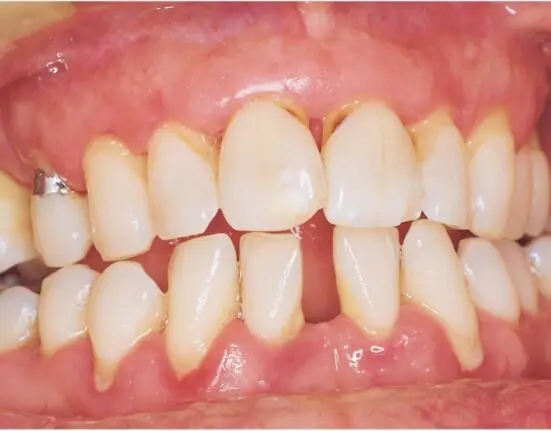

Chronic periodontitis is a risk factor for dementia, according to researchers at Seoul National University in South Korea who examined information from the National Health Insurance Service-Health Screening Cohort (NHIS-HEALS).

Those with chronic periodontitis had a 6% higher risk for dementia than those without it. This connection was true despite behaviors such as smoking, alcohol consumption, and physical activity.